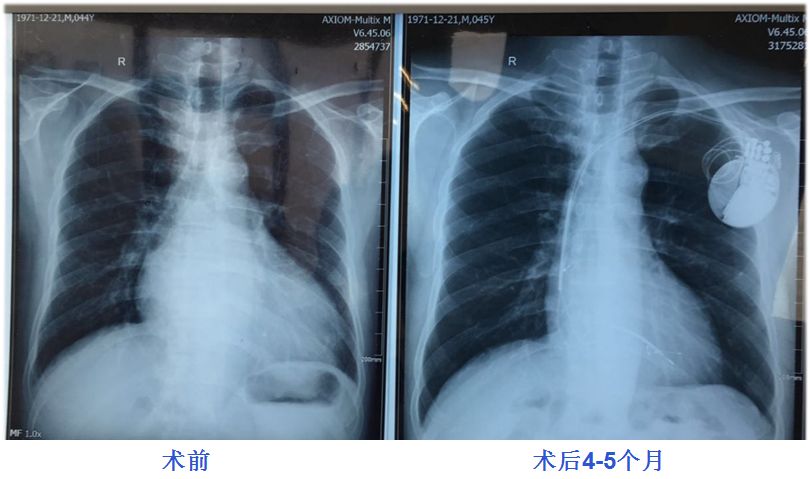

术前:QRS宽度平均160ms降至120ms

术后4-5个月:V1、V2导联P波直立